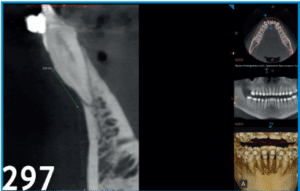

L’utilisation quotidienne du Cone Beam (CBCT) en orthodontie, notamment pour les patients fragilisés par la maladie parodontale est d’un intérêt croissant. Traditionnellement, l’analyse parodontale reposait sur des outils 2D comme les radiographies panoramiques, le sondage et les clichés photographiques. Le CBCT, imagerie 3D de haute précision, devient un outil de plus en plus utilisé, offrant une visualisation tridimensionnelle des structures osseuses et dentaires, difficile à obtenir en 2D. Il permet une meilleure évaluation des pertes osseuses, des déhiscences, des fenestrations, et de la morphologie des furcations, facilitant ainsi la planification des traitements orthodontiques et parodontaux complexes. Les recommandations insistent sur une utilisation raisonnée du CBCT, en privilégiant les plus petits champs de vue (FOV) pour limiter l’irradiation, et uniquement lorsque les examens 2D sont insuffisants. En phase de maintenance, le CBCT aide à surveiller l’évolution de la maladie parodontale. En conclusion, le CBCT améliore la sécurité et la prévisibilité des traitements orthodontiques chez les patients à risque parodontal, tout en respectant les principes de radioprotection.